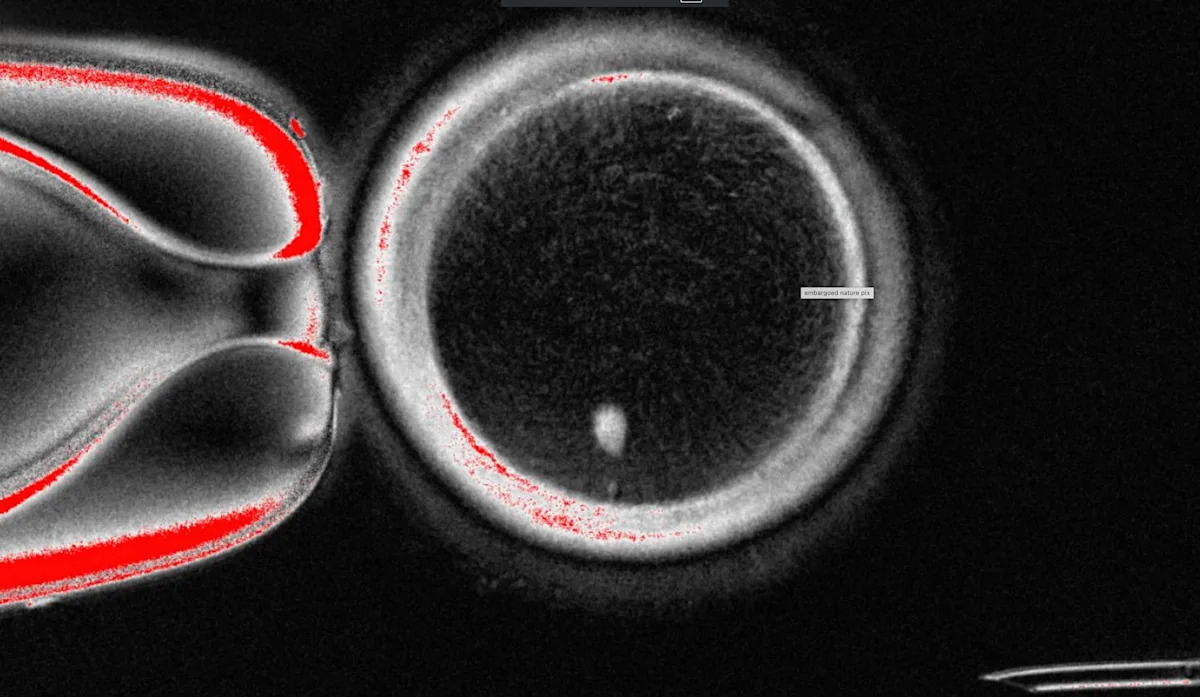

قام فريق OHSU بإزالة النواة من خلية البيض البشرية واستبدلها بالنواة من خلية الجلد البشرية. ولكن تحتوي خلية الجلد على مجموعتين من الكروموسومات ، ومن المفترض أن تحتوي كل من البيض والحيوانات المنوية على مجموعة واحدة فقط تجمع أثناء الإخصاب. لذلك ، حث الباحثون على خلايا تشبه البيض لتجاهل الكروموسومات الإضافية ، وحقن الحيوانات المنوية المتبرع بها وتطور ما بعد الإخصاب.

استمر حوالي 9 ٪ لمدة ستة أيام في أطباق المختبر ، حيث وصلوا إلى مرحلة الكيسة الأريمية من تطور الجنين المبكر ، قبل توقف التجربة.